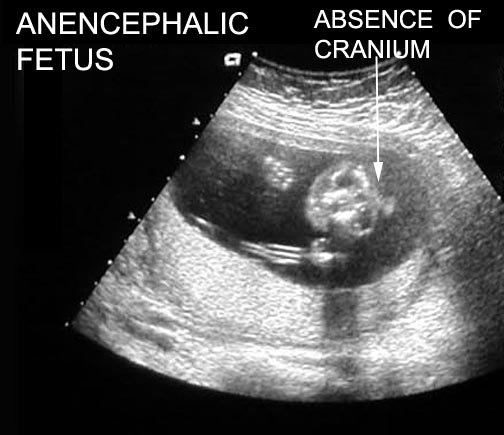

Anencephaly

www.stritch.luc.edu